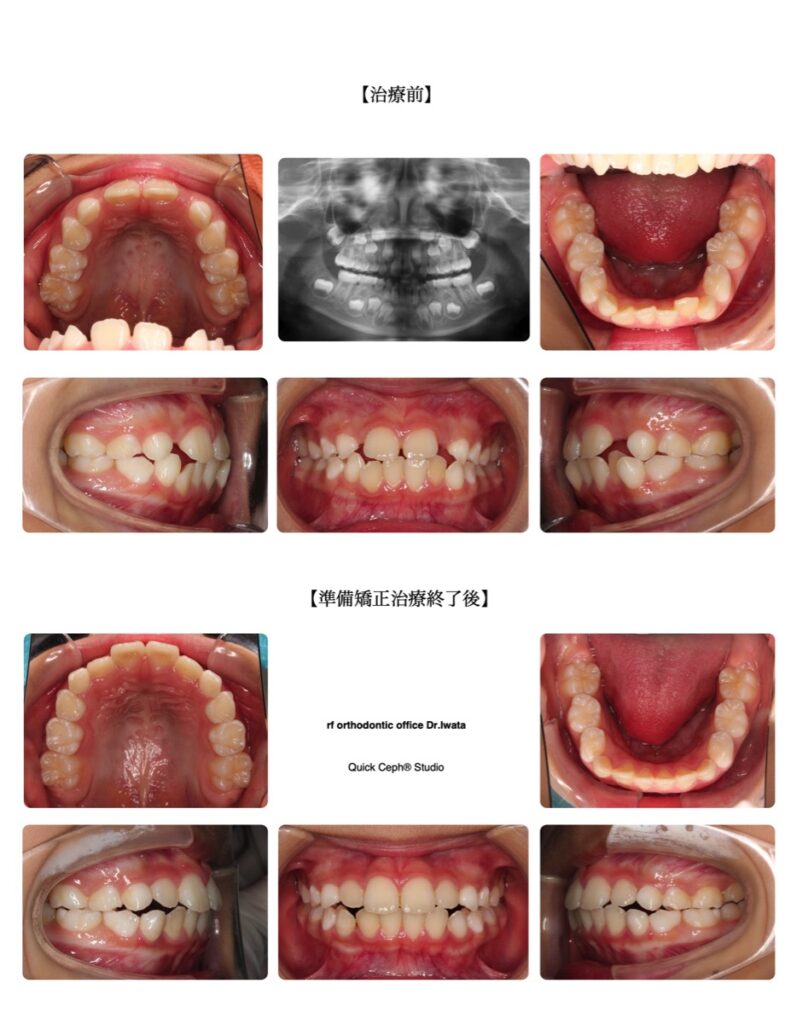

叢生症例 <切端咬合を伴う叢生に対する準備矯正治療>

【主訴】上の前歯はすきっ歯だけど横の前歯がスペースが足りなくてなかなか生えてこない。下の前歯のガタガタも強くて今後の歯並びが心配。

【主な症状】叢生 上下顎前突

| 治療期間 | 11ヶ月 |

| 年齢 | 7歳 |